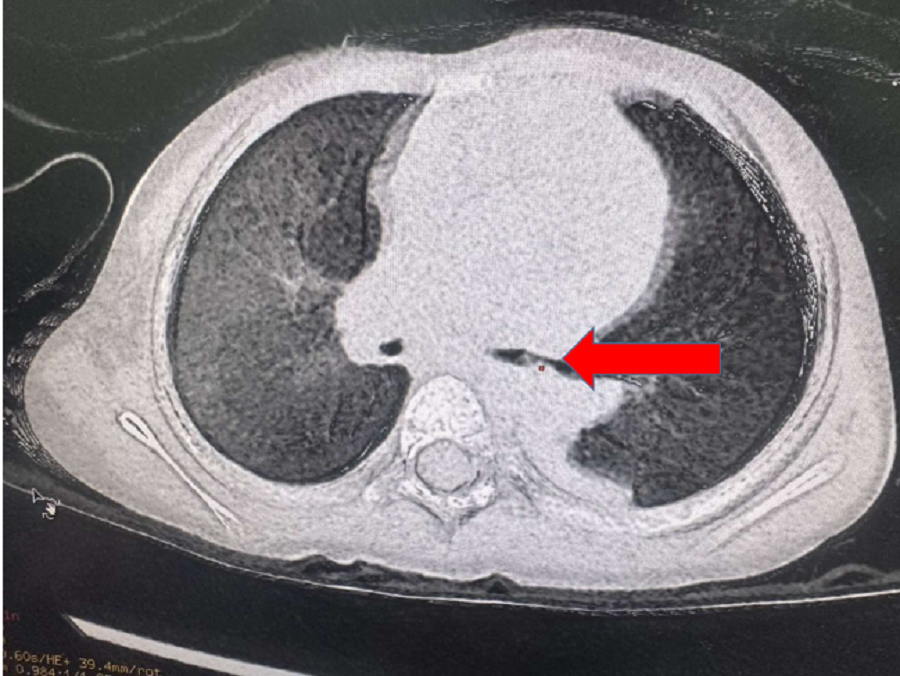

| Hình ảnh kiểm tra ghi nhận dị vật lấp đầy phế quản bên trái của bệnh nhi |

Tại Bệnh viện Nhi đồng Thành phố, khi chụp X-quang phổi, các bác sĩ phát hiện bệnh nhi bị ứ khí phổi trái. Kết quả CT-Scan phổi ghi nhận nhiều tổn thương dạng đông đặc ở thùy trên và giữa phổi phải, nhiều phân thùy của phổi bên trái bị xẹp, ứ khí. Các bác sĩ đã phát hiện hình ảnh dị vật lấp đầy phế quản bên trái.